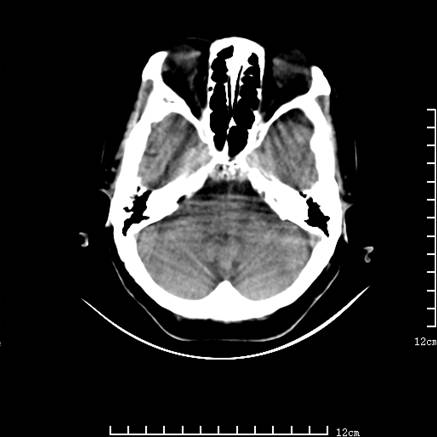

标题: V0514:女,72岁,偶有头晕,自诉记忆力减退,来诊。 [打印本页]

标题: V0514:女,72岁,偶有头晕,自诉记忆力减退,来诊。

1、考虑垂体腺瘤。

2、脑萎缩ct表现。

垂体腺瘤可能性大!另:轻度脑萎缩!

考虑垂体腺瘤可能性大。脑萎缩。

考虑垂体腺瘤可能性大。脑萎缩。  建议mri 检查

垂体瘤,建议mri

垂体腺瘤